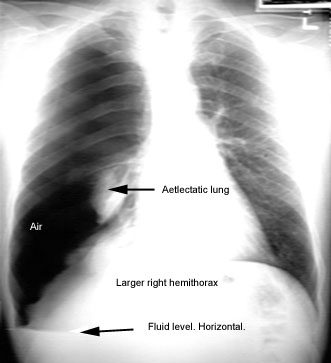

Note air on top and effusion on bottom.